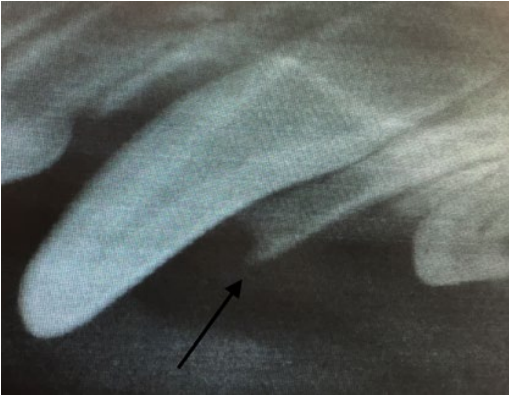

- Неправильная траектория прорезывания (фото 2). Такая патология может возникать из-за нарушения развития альвеолярного отростка в результате какого-либо механического препятствия, нарушения закладки зачатков зубов в раннем эмбриональном периоде, а также по причине дефицита места.